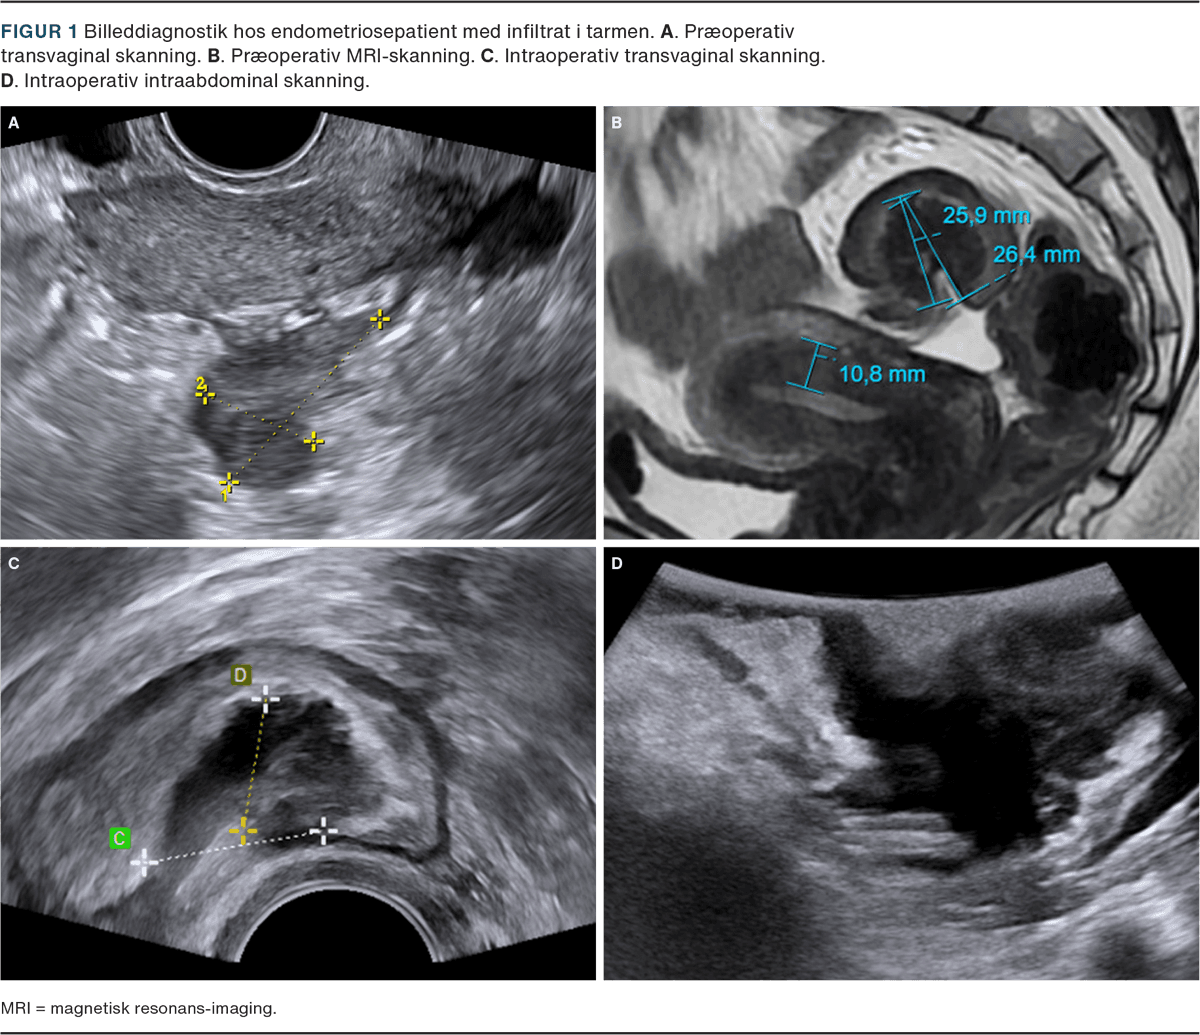

I dag anser man, at sikre tegn på endometriose påvist ved enten transvaginal UL-skanning (TVUS) eller MR-skanning er tilstrækkeligt til at stille diagnosen, se Figur 1. TVUS bør udføres systematisk, hvor man udover skanning af ovarier, uterus, blære og tarm også bemærker mobilitet og ser efter endometrioseinfiltrater i fossa Douglasi, blære og tarm i henhold til international deep endometriosis analysis (IDEA) group protokollen [26]. MR-skanning anvendes primært på højt specialiserede centre. Manglende billeddiagnostisk forekomst af endometriose udelukker dog ikke diagnosen.